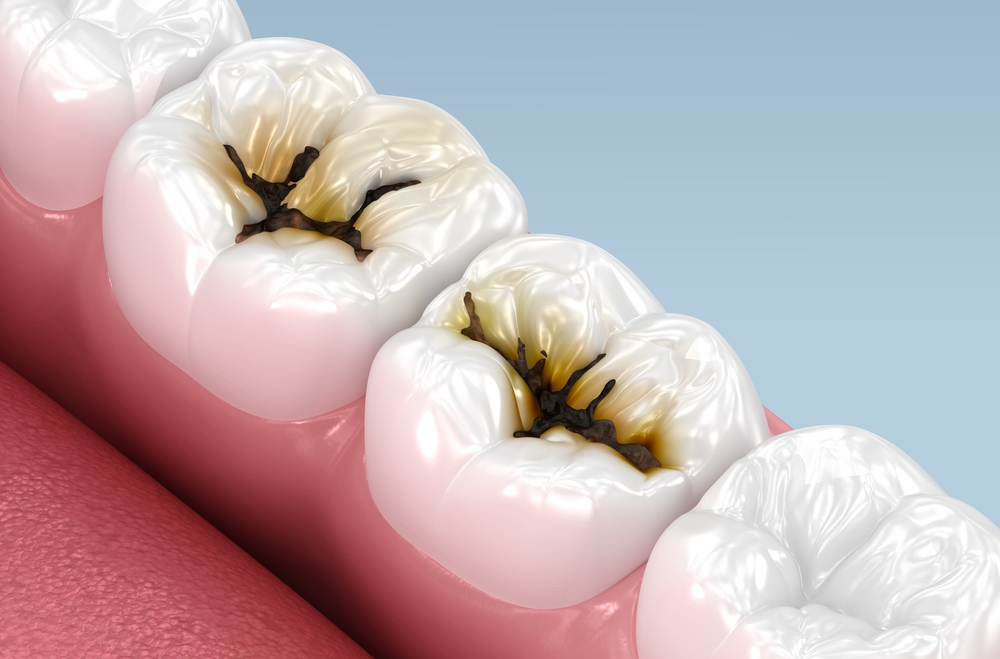

일상에서 치아가 예전보다

더 예민하게 느껴지거나,

음식을 먹을 때 불편함이 반복된다면

내부까지 변화가

진행된 것일 수 있습니다.

이러한 변화는 겉으로 보기에는

큰 차이가 없어 보일 수 있지만,

치아 깊은 부분이 영향을

받기 시작하면 생활 속에서

여러 불편함이 나타나곤 합니다.

치과에서는 치아 겉면의 깨어짐이나

색 변화뿐 아니라, 내부에 어떤 영향이 있는지

먼저 확인하는 방식으로 접근합니다.

충치가 깊어졌다면 단순히 바깥 부분만

정리하는 것으로는 부족하며,

정리하자면, 충치가 깊어져 불편함이

반복된다면 시간을 두기보다는 현재

상태를 빠르게 확인하는 것이 좋습니다.

겉으로 보기에 큰 변화가 없어도

내부가 영향을 받는 경우는 흔하기 때문에,